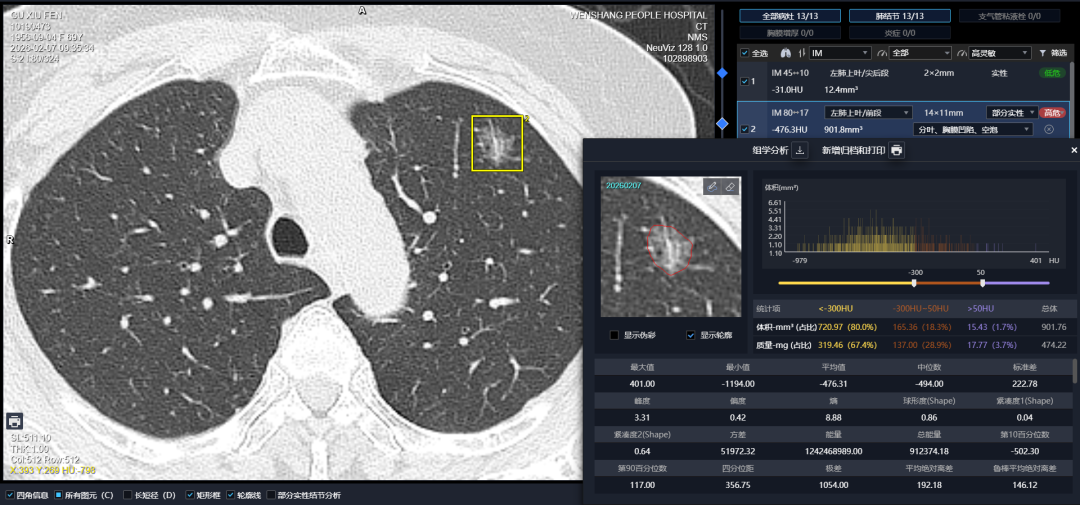

精准筛查是肺结节诊疗的第一步。汶上县人民医院在CT筛查领域率先实现“双智能化”升级,引入两套顶尖AI辅助系统——深睿医疗及联影智能模块,均实现长期正式部署与HIS系统深度融合,打造县域少有的“双AI协同”筛查模式。为群众提供更精准、更可靠的筛查服务,开启肺结节精准筛查“双保险”时代。

两套AI一起干活有什么好处?

算法不同,侧重点不同,相当于两个顶尖专家一起看片,互相核对;1毫米的小结节、淡淡的磨玻璃影,人眼容易漏,AI一抓一个准;能精准量出结节的尺寸、密度,还能对比对历史影像、量化结节变化,为长期随访和诊疗决策提供核心依据。

“两套AI互相印证,遇到疑难影像也会主动‘报警’,医生再启动人工复核,最大程度避免漏诊误诊。”心胸外科闫春章主任介绍道。